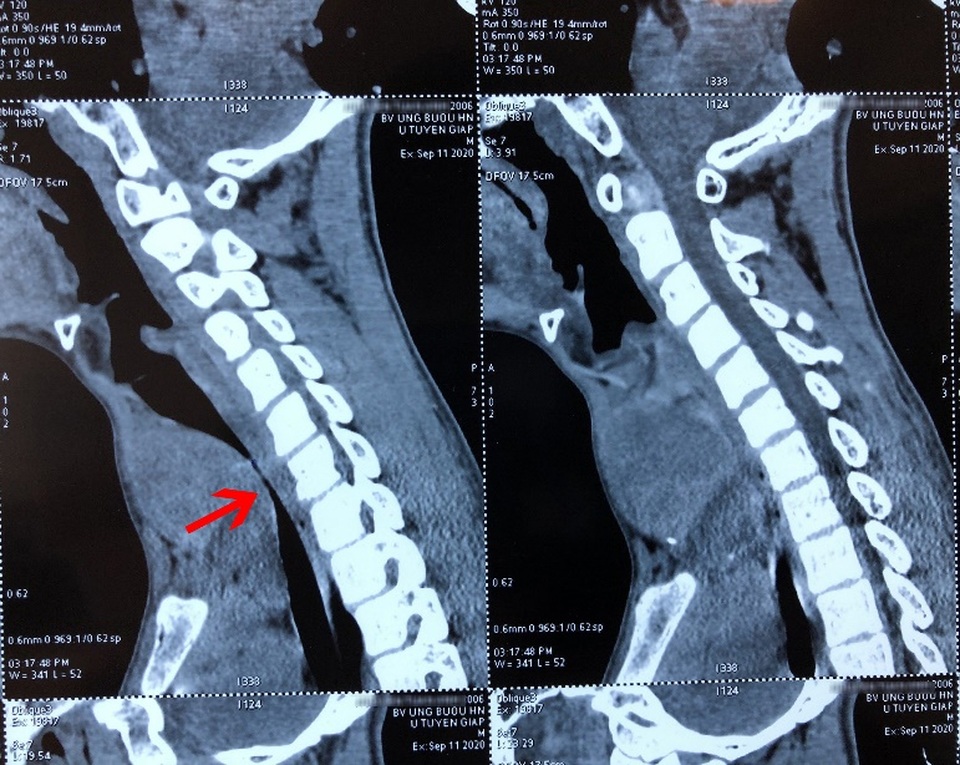

Tại BV Ung bướu Hà Nội, các bác sĩ xác định bệnh nhân bị khối u thùy giáp trái đã di căn phổi đa ổ, lan xuống hõm ức, kích thước 8x9cm đè ép khí quản lệch hẳn sang phải gây hẹp lòng khí quản.

"Khối u chèn ép khiến khí quản bệnh nhi chỗ hẹp nhất chỉ còn 4mm (người bình thường đường kính khí quản khoảng 12mm) khiến bệnh nhân khó thở, như cá mắc trên cạn. Khối u cũng khiến giọng nói của A. biến đổi, khàn đặc, khó ăn uống", BS điều trị cho biết.

Khối u chèn ép gây hẹp lòng khí quản, chỗ hẹp nhất chỉ còn 4mm khiến bệnh nhân khó thở, ăn uống khó.